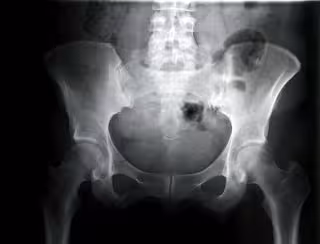

Cadera de mujer vista con rayos.

El 22 por ciento de los pacientes que sufren displasia de cadera tratados durante el primer año de vida desarrollarán displasia residual, cifra que aumenta hasta el 64 por ciento a partir de los 2 años, según ha destacado el doctor Juan Cabello Blanco, director del curso y traumatólogo infantil de Clínica CEMTRO (Madrid), quien ha concluido que el diagnóstico precoz supone un "importante" cambio en el pronóstico del afectado.

La displasia de cadera es una enfermedad ósea y hereditaria que actualmente presenta una prevalencia de entre el 1 y 7 por ciento, según ha destacado la Sociedad Española de Pediatría Extrahospitalaria y Atención Primaria (SEPEAP). Es más común en niñas y entre sus principales factores de riesgo destacan la posición podálica intraútero y los antecedentes familiares.